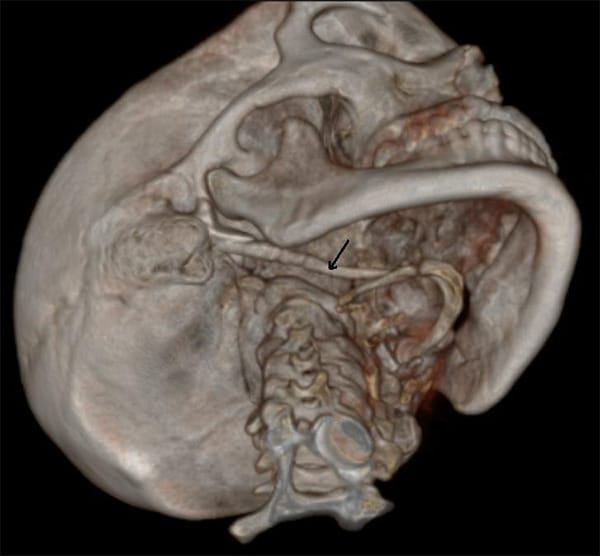

Eagle syndrome is a rare condition where the styloid process becomes elongated or the stylohyoid ligaments become calcified. When the process elongates, it can constrict nerves, the carotid artery, and create a variety of symptoms that are often misdiagnosed. (see Image 1 and 2)

Image courtesy Dr. Jadon Ashok, CC BY-SA 4.0 https://creativecommons.org/licenses/by-sa/4.0, via Wikimedia Commons.

Radiographic Imagery

Is the styloid process approximately 2.5cm, or has it elongated? How does the TMJ look? If the styloid process is elongated and the TMJ looks relatively normal, a referral to an ear, nose, and throat specialist (ENT) is advised.

The ideal radiologic review is with 3D computed tomography. However, many dental offices do not have this imagery available.4 The referral to an ENT for further examination should be recommended if a patient does not respond to TMD therapy, NSAIDs, or when radiographs do not reveal any significant temporal mandibular disorder (TMD) issues.